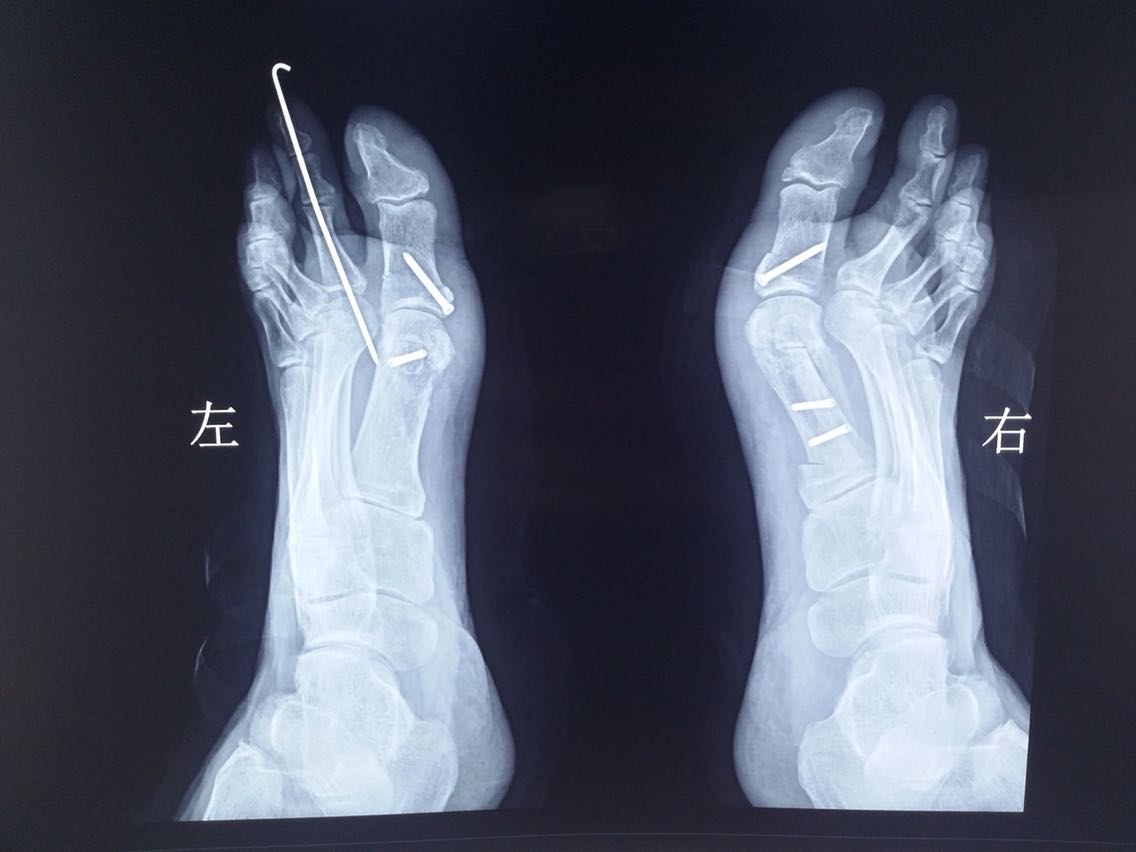

主诉:双足第一趾外翻畸形10余年。 病史:患者F/55,自述双足无明显诱因出现第一趾外翻畸形10余年,长时间行走或工作劳累后出现疼痛,近2年来症状加重。

查体及辅助检查:双足第一趾重度外翻畸形,第一趾长轴与第一跖骨长轴夹角>25°,第一、二跖骨头夹角>9°。

诊断:双足拇外翻畸形 治疗:截骨矫形修复术